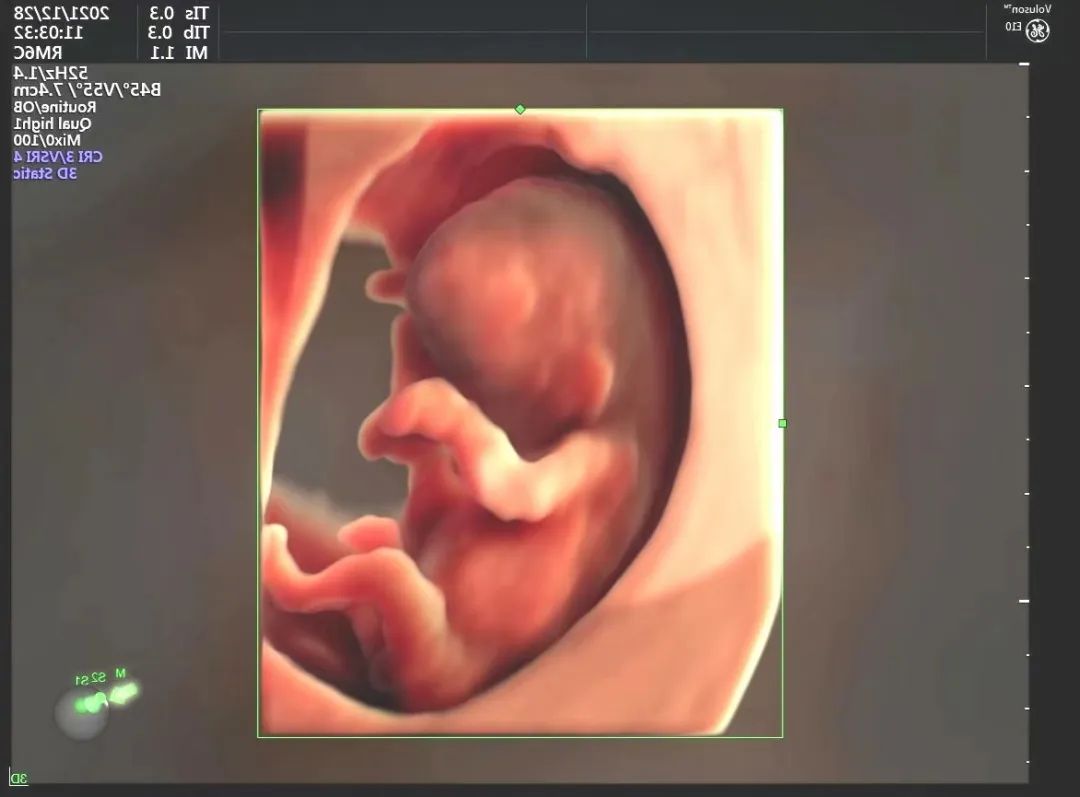

1.胎儿系统产前筛查——即人们常说的“大排畸”,是应用高分辨率的彩色多普勒诊断仪对胎儿进行全身系统的畸形筛查及诊断。其主要目的是为了检查胎儿是否患有重大畸形,对胎儿的大脑、颜面部、心脏、腹部、四肢等结构进行逐一筛查。

5.超声声学造影及三维、四维立体成像技术——超声声学造影被誉为“无创性微循环血管造影”,具有高准确性、高安全性、操作简便、重复性好的特点。适应症:①肿瘤定性(良、恶)诊断;②微小病灶早期发现;③介入治疗后的疗效评估。二维是平面成像,三维是立体成像,四维是三维加上时间的维度,即动态的三维,通过表面成像模式、骨骼成像模式、血管成像模式等由计算机进行三维重建。